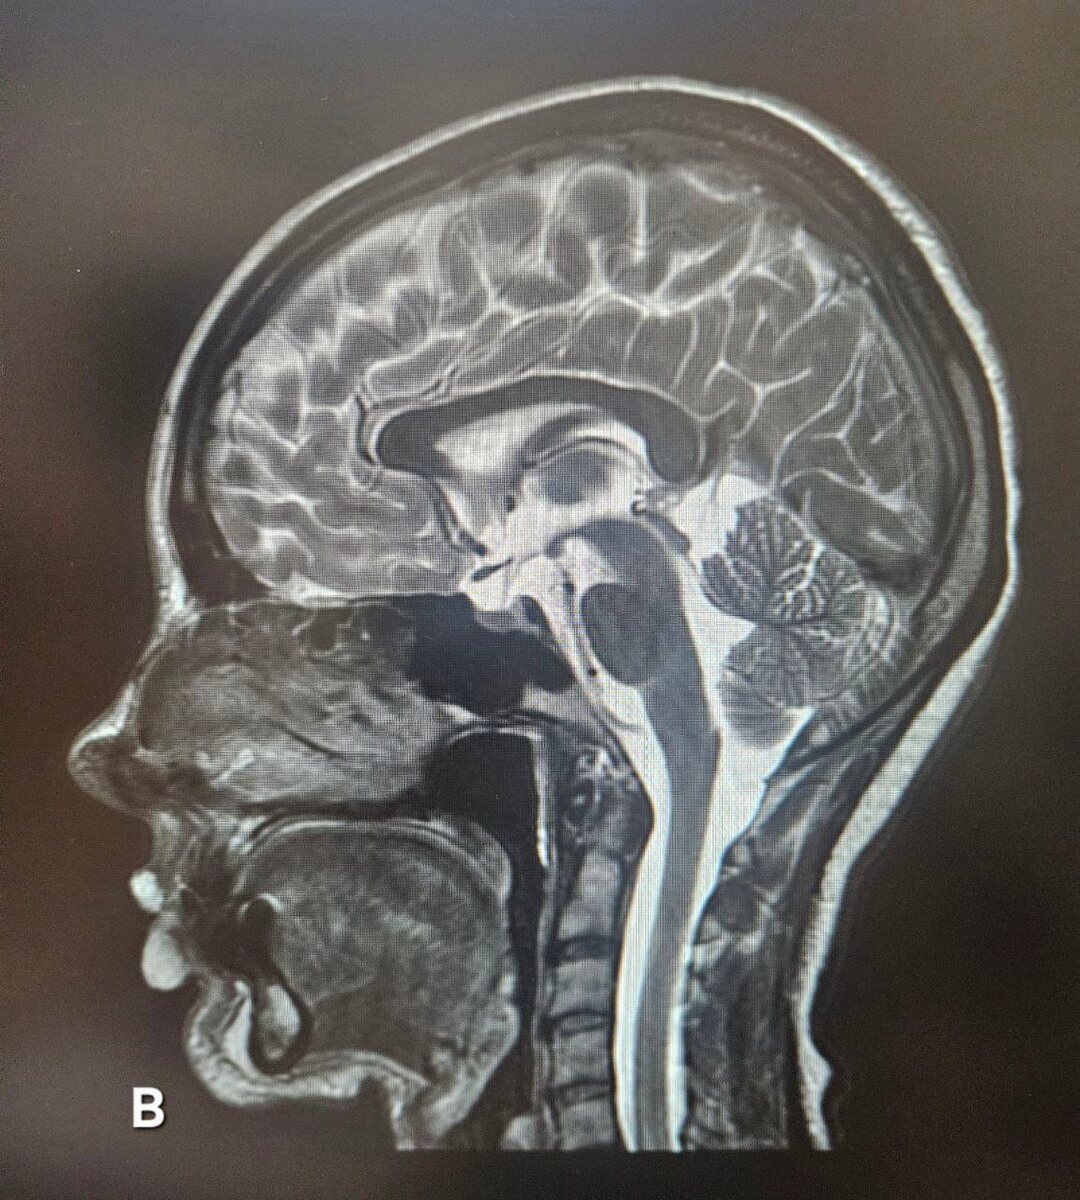

МРТ мужчины 😠 и женщины 💅